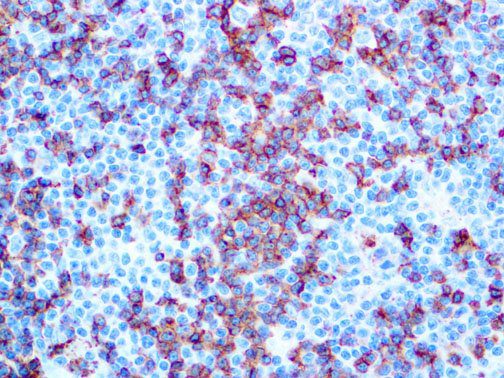

The first cytokines released are interleukin 1β (IL-1β) and tumor necrosis factor-α (TNF-α), which attract a variety of circulating white blood cells (WBCs) to the infection site, including neutrophils, monocytes, macrophages, and natural killer (NK) cells. This response, along with the antipathogenic chemicals released by these cells (i.e., complement), comprise the innate immune response. These cells directly attack the invading pathogen and also release additional cytokines, chief among them interleukin-1 and 6 (IL-6). IL-6 is essential for invoking the adaptive immune response, which calls T-cells, B-cells, and T helper (Th) cells to the infection site. IL-6 also stimulates further recruitment, proliferation and activation of macrophages.

It is the ICU physician who is most likely to witness one of the deadliest manifestations of the abnormal immunological response, the cytokine storm syndrome (CSS). This response is also referred to by some as the cytokine release syndrome (CRS). CSS is characterized by continuous activation and expansion of macrophage and lymphocyte populations, which secrete large amounts of cytokines, causing the cytokine storm. This massive cytokine release is akin to hemophagocytic lymphohistiocytosis (HLH) disease, a syndrome characterized by initial unchecked and persistent activation of cytotoxic T lymphocytes and NK cells.